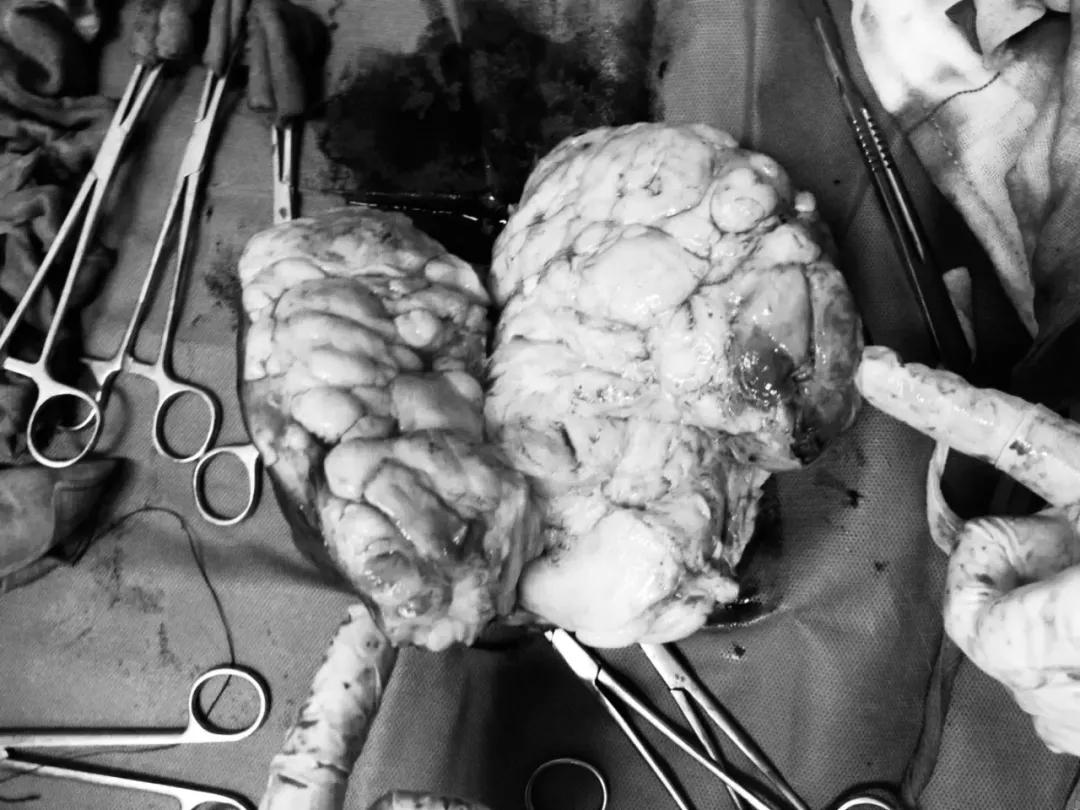

▲让黄姨变“结实”的肌瘤

▲让严姨“长胖”的肉瘤